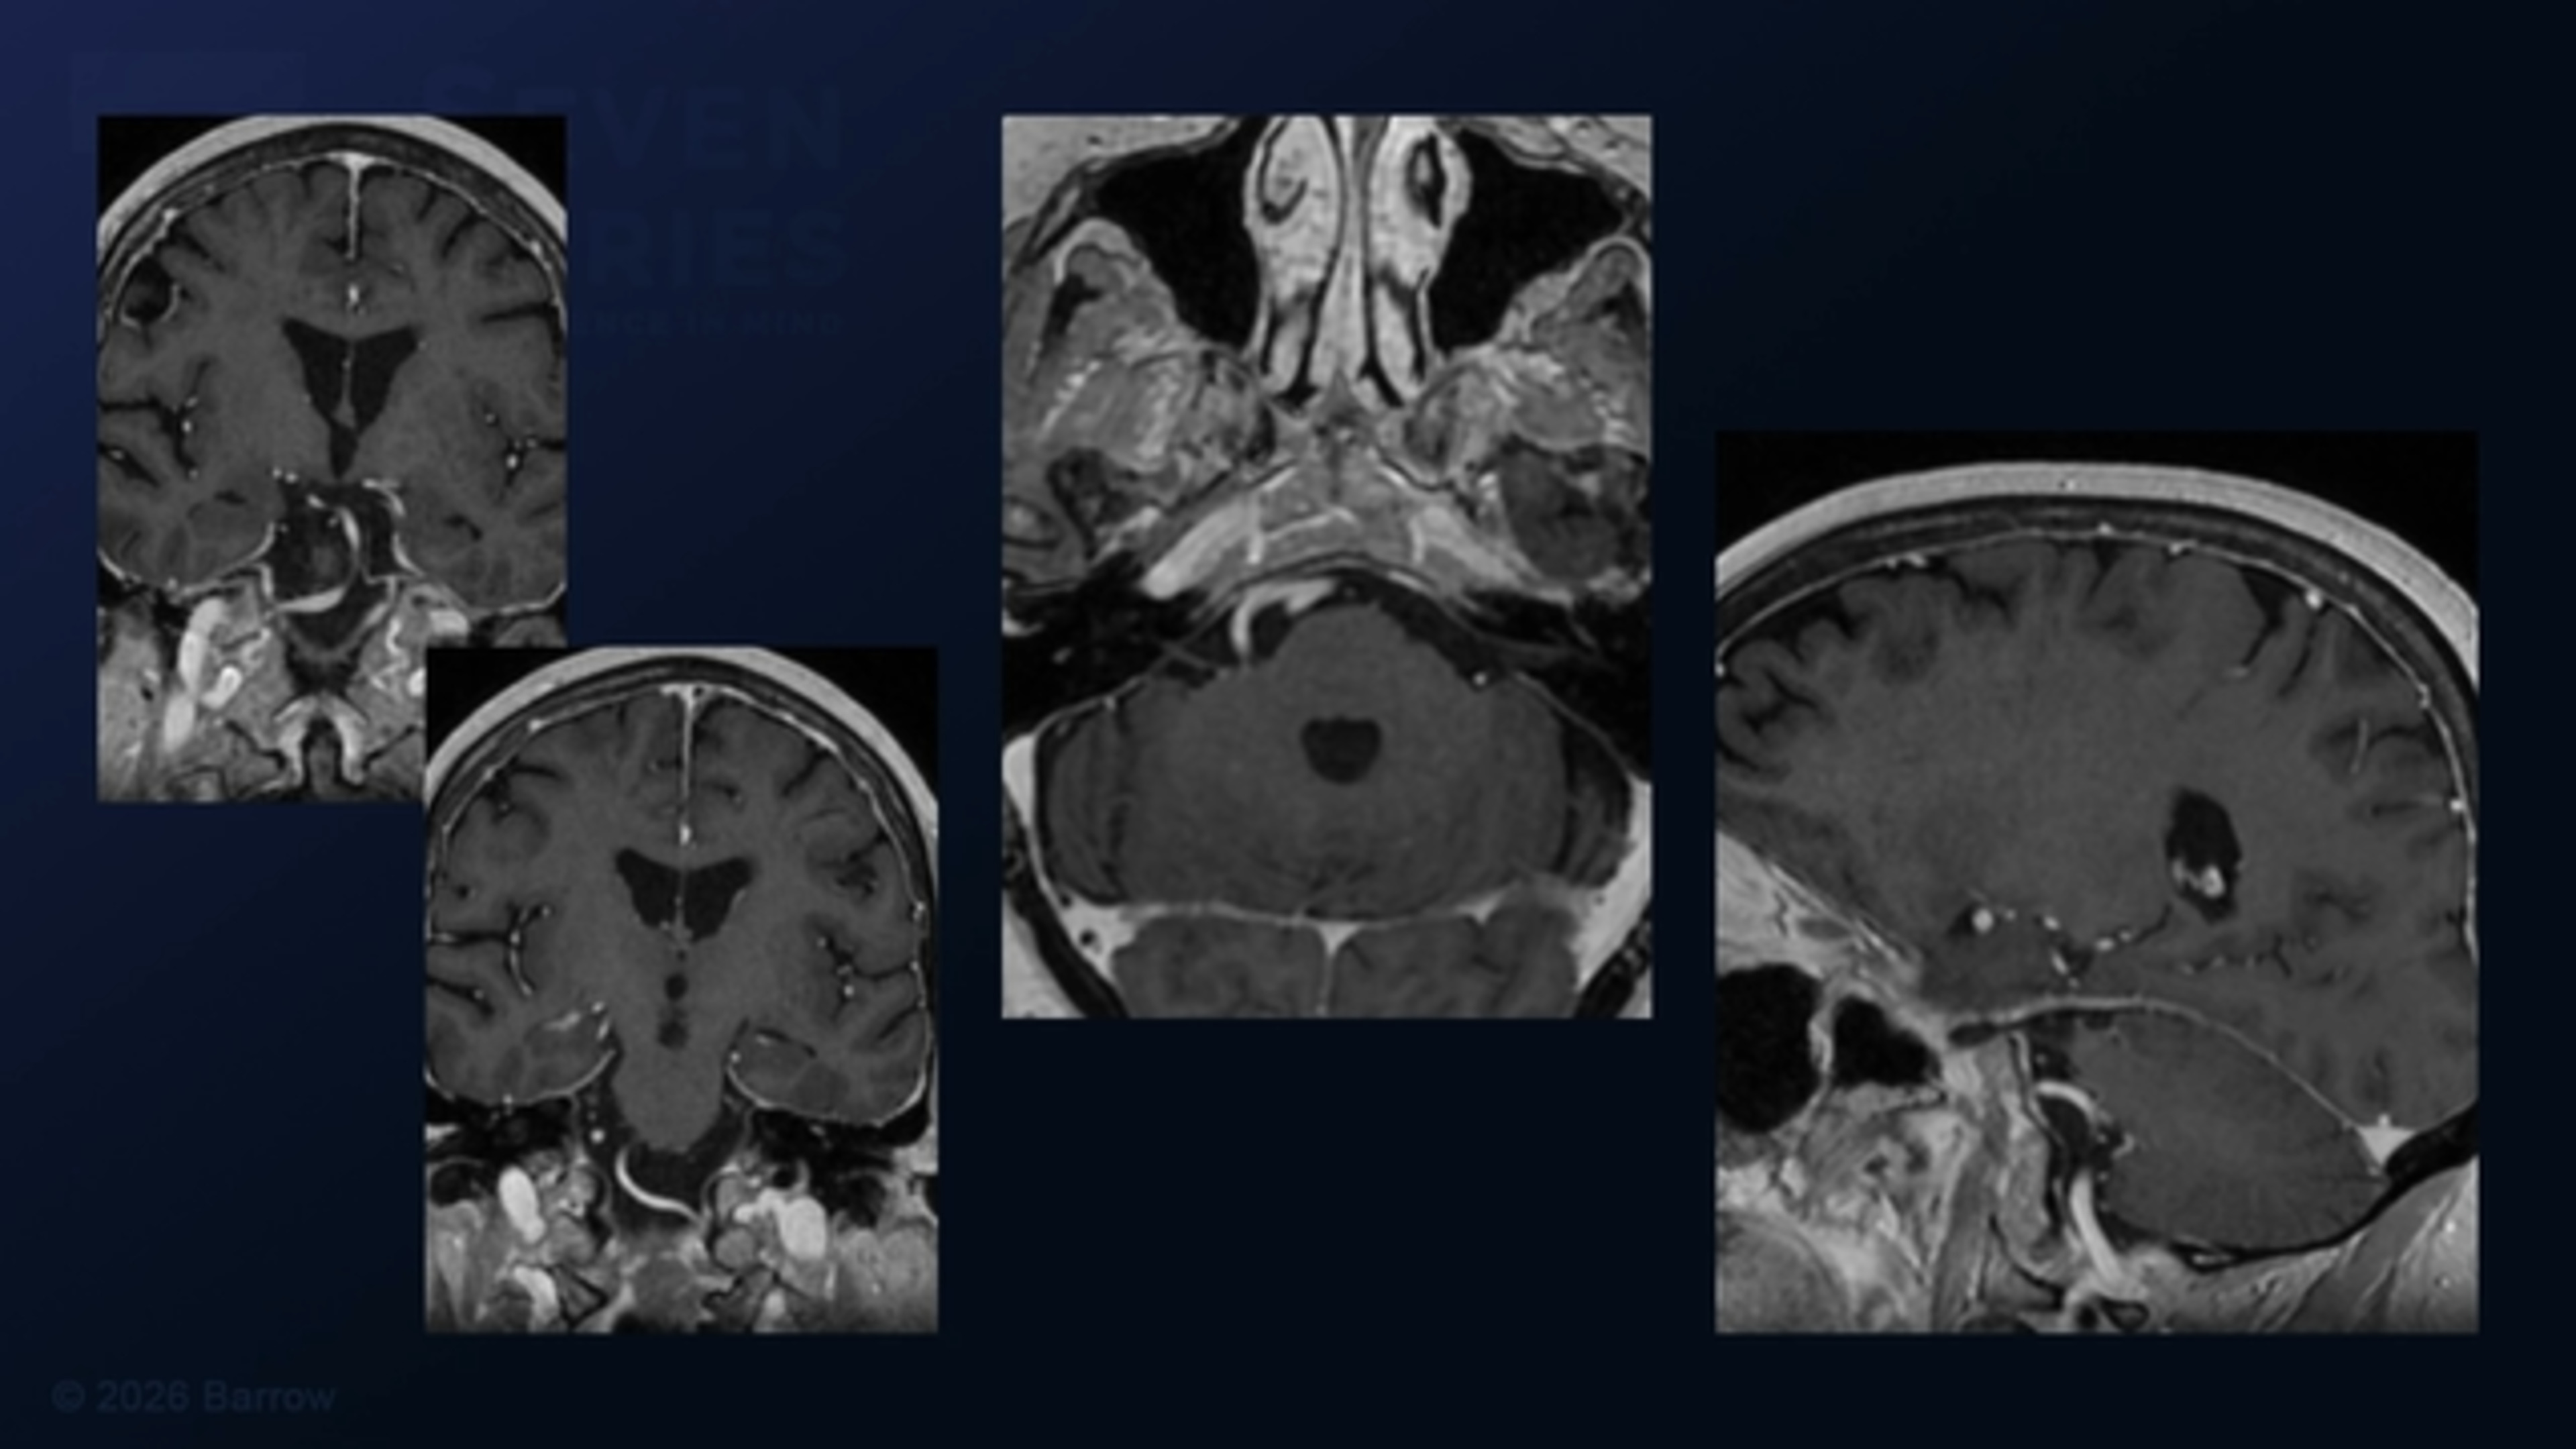

#510: Macrovascular Decompression of the Right V4 Vertebral Artery for Hemifacial Spasm

Episode 510 of Seven Series shows a macrovascular decompression of the right V4 vertebral artery for hemifacial spasm.